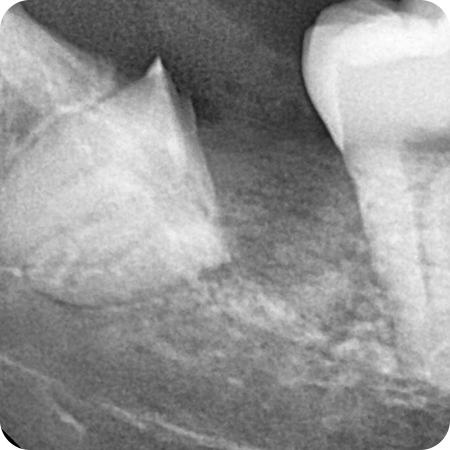

이제 사랑니 발치도 편안하게

사랑니 발치

사랑니의 위치적 특징으로 고난도 발치가 많습니다.

이제 사랑니 발치는 으뜸원에서 해드리겠습니다.

사랑니 발치가 어려운 이유

신경관과 같은 해부학적 구조물에 가깝고

매복된 위치와 각도에 따라 잇몸 및 골 삭제 과정이

추가적으로 필요합니다.

사랑니 발치 으뜸원인 이유

전문 장비를 이용해 정확한 진단을 하고

통합치의학과 전문의의 노하우를 바탕으로

안전하게 사랑니 발치를 합니다.

상악 사랑니 발치

상하악 사랑니발치

하악 사랑니 발치